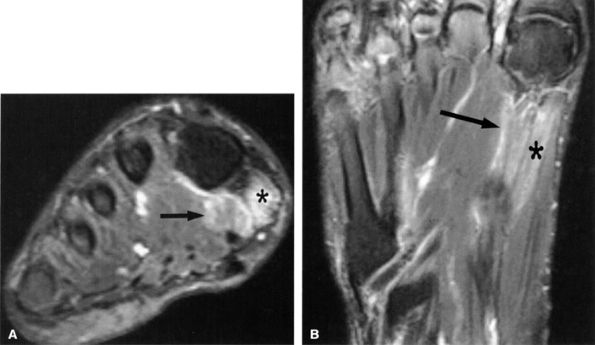

Denervation of the first lumbrical and of the flexor hallucis brevis muscle, also consistent with medial plantar nerve entrapment, is better seen on MR images of the foot (Figs. 6.53 and 6.54).

FIGURE 6.53 ● Medial plantar neuropathy. Oblique coronal (A) and axial (B) fluid-sensitive fat-suppressed images of the foot show denervation edema in the flexor digitorum brevis (arrow) and abductor hallucis (asterisk) muscles.

FIGURE 6.54 ● Medial plantar neuropathy. Oblique coronal T1-weighted image of the foot shows denervation atrophy of the flexor digitorum brevis muscle (arrow).

|